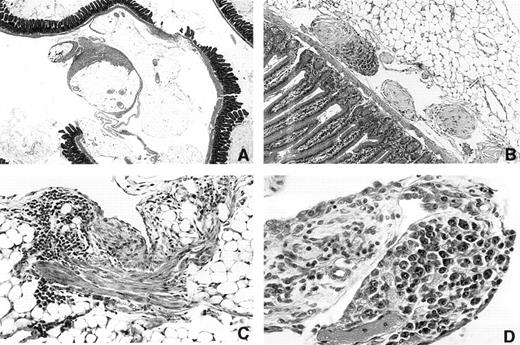

Inhibition of plastic disc induced PCT formation by INDO.When it was clear that mice could be maintained on INDO in the drinking water for more than 300 days, it became possible to determine if INDO could inhibit induction by plastic discs. This was of special interest because on-going histological studies of mice bearing i.p. discs indicated that this kind of foreign body produced a very different pathological response than was seen with oils. Essentially, there was no accumulative granuloma deposition on mesenteric surfaces, but instead the discs induced a patchy fibroplastic reaction (Fig 4A and C) that varied in amount from mouse to mouse. Occasional polyp-like structures containing collagenous material was seen near the mesenteric attachment sites (Fig 4B). The omentum was frequently adherent to the disc and appeared thickened. Most plastic discs were found to be adherent to the peritoneal connective tissues of the abdominal wall or omentum. An occasional disc was found in the retroperitoneum. In a few mice the disc was unattached. Varying numbers of adhesions of disc to intestine, omentum, abdominal fat, or abdominal wall were found. The discs themselves were also covered by a tenacious fibrous capsule. Adhesions of the discs to the omentum often contained blood vessels. It was suspected that in some of the mice this connective tissue bridge was broken as the surfaces of some of the disc contained piled-up necrotic tissue. The PCTs, however, did not appear to develop in the dense fibroplastic tissue as they were found either in the omental connective tisues (Fig 4D) or were first detected as multiple growths attached to or within small fibrotic polyp-like structures (Fig 4B).

Photomicrographs of peritoneal surfaces in mice carrying Lucite 21× 2 mm plastic discs. (A) 3616 1.5 × 2× Day 315. Section through mesenteric fat and intestine showing patchy fibrous deposition on mesothelial surfaces of mesenteric fat. Note that much of the surface is not covered. (B) 3173 20 × 10× Day 214. Region near the mesenteric attachment site containing three polyp-like structures. The two light staining polyps contain fibrinoid tissue covered with mesothelium. The third polyp is invaded by plasmacytoma cells. (C) 3164 20 × 5× Day 214. A patch of fibrous tissue on a fat surface on the left. The tissue contains numerous lymphocytes. (D) 3333 20 × 5× Day 258 Vascularized polyp-like structure arising from the omentum that contains a focus of atypical plasma cells. This was the only plasma cell lesion found in this mouse.